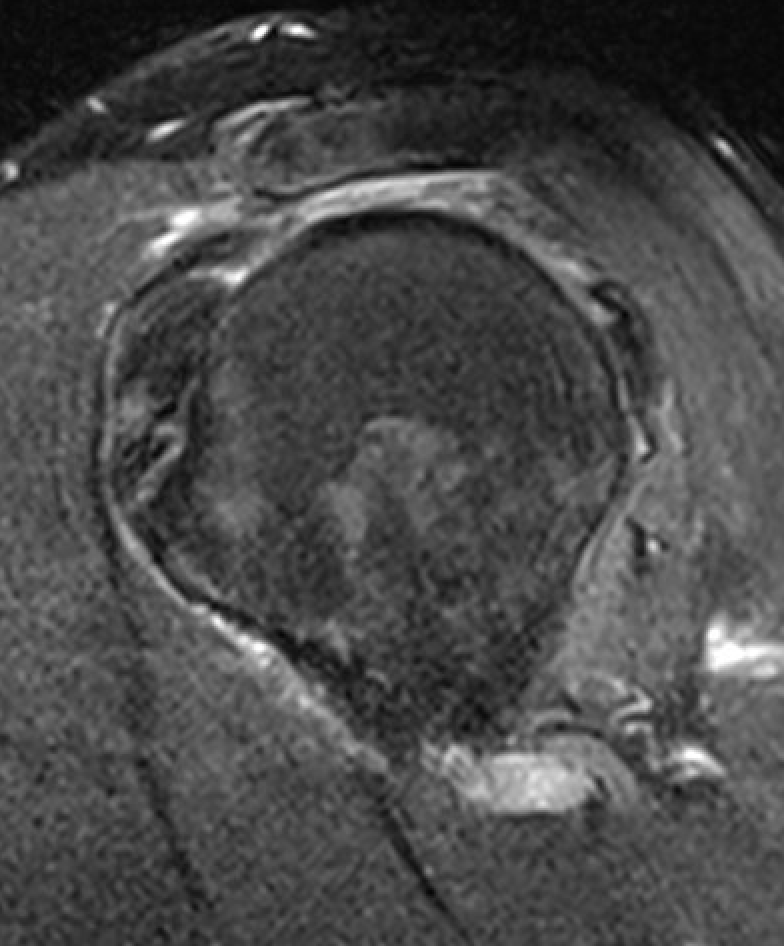

Goutallier classification

Amount of fatty degeneration in rotator cuff muscle belly on a T1 sagittal MRI

- systematic review of Goutallier grade and retear rates

- retear rates after surgical repair increase as the Goutallier stage increases

Stage 0: normal muscle

| Stage 1 | Stage 2 |

|---|---|

|

Some fatty streaks MRI shows some fatty streaks in supraspinatus |

More muscle than fat MRI shows grade 2 in supraspinatus |

|

|

| Stage 3 | Stage 4 |

|---|---|

|

Equal fat and muscle MRI demonstrates grade 3 supraspinatus and infraspinatus |

More fat than muscle MRI demonstrates grade 4 infraspinatus |

|